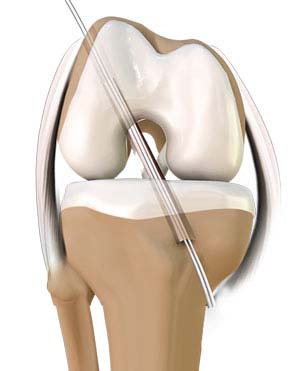

Anatomy of the ACL

The anterior cruciate ligament is one of the major stabilizing ligaments in the knee. It is a strong rope-like structure located in the center of the knee, running from the femur (thighbone) to the tibia (shinbone). The ACL is one of the four major ligaments of the knee that connects the femur to the tibia and helps stabilize your knee joint. It prevents excessive forward movement of the tibia in relation to the femur as well as limits rotational movements of the knee. When this ligament tears, unfortunately, it does not heal on its own and often leads to the feeling of instability in the knee, requiring reconstruction to correct the abnormality.

ACL reconstruction surgery is usually performed under general anesthesia using a minimally invasive arthroscopic technique. In general, the procedure involves the following steps:

- Your surgeon will make two to three small cuts, about 1/4-inch-long, around your knee.

- An arthroscope is inserted into the knee joint through one of the incisions.

- An arthroscope is a thin tubular instrument with a camera, light, and a magnifying lens attached at the end that is connected to an external monitor and enables your surgeon to view the inside of the knee joint.

- Along with the arthroscope, a sterile solution is pumped into the joint to expand it, enabling your surgeon to have a clear view and space to work inside the joint.

- Miniature surgical instruments are passed through the other incisions and the torn ACL is removed and the pathway for the new ACL tendon graft is prepared.

- Your surgeon makes an incision over the knee or hamstring area and takes out a part of the patellar, hamstring, or quadriceps tendon to prepare the new ACL graft.

- Small holes are drilled into the upper and lower leg bones (femur and tibia) where these bones come together at the knee joint. The holes form tunnels in your bone to accept the new graft.

- The graft is pulled through the predrilled holes in the femur and tibia and fixed into the bones with screws or suture anchors.

- After confirming satisfactory reconstruction, the scope and the instruments are withdrawn, and the incisions are sutured and bandaged.